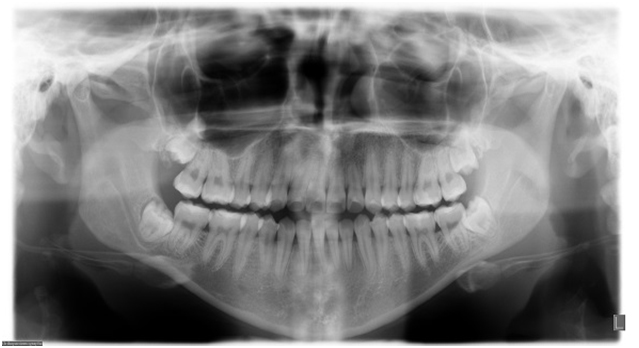

In the seven orthopantomographies with carotid calcifications, 57.1% (4) were bilateral and (42.9%) 3 unilateral (Table 1) (Figure 1).

Figure 1. Patient 1-7